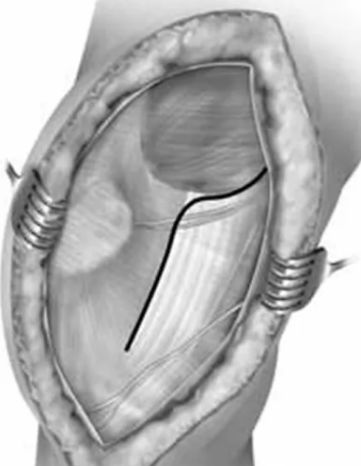

沿股骨外髁与Gerdy结节后缘连线作5cm左右纵行切口,可根据情况向上下延伸(如下图)。

直接外侧入路虽然可以显露股骨远端及外侧部分,但由于髂胫束的遮挡,对股骨髁后侧部分显露不够充分。

直接外侧入路适用于部分骨折块较大的Letenneur I、III型外髁Hoffa骨折,对II型(完全囊内骨折、靠后)及后髁粉碎者不适合。